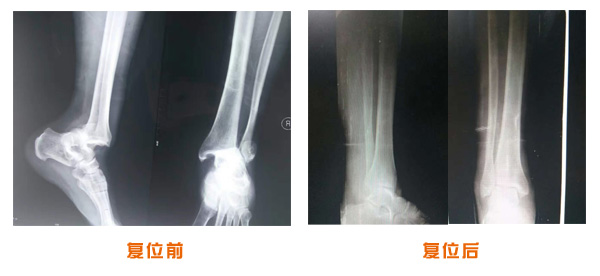

肥城市安駕莊梁氏骨科醫(yī)院是一所以梁氏手法正骨配合膏藥為特色的現(xiàn)代化專科醫(yī)院。

梁氏骨科術(shù)始創(chuàng)于清雍正年間,歷經(jīng)八代,至今已有三百年歷史。據(jù)1929年泰安縣志載“梁瑞圖先生,字增生,號蓮峰,安駕莊人,精岐黃并發(fā)明接骨,凡跌打車凡跌打車軋皮不破而碎骨者......【詳細】 |